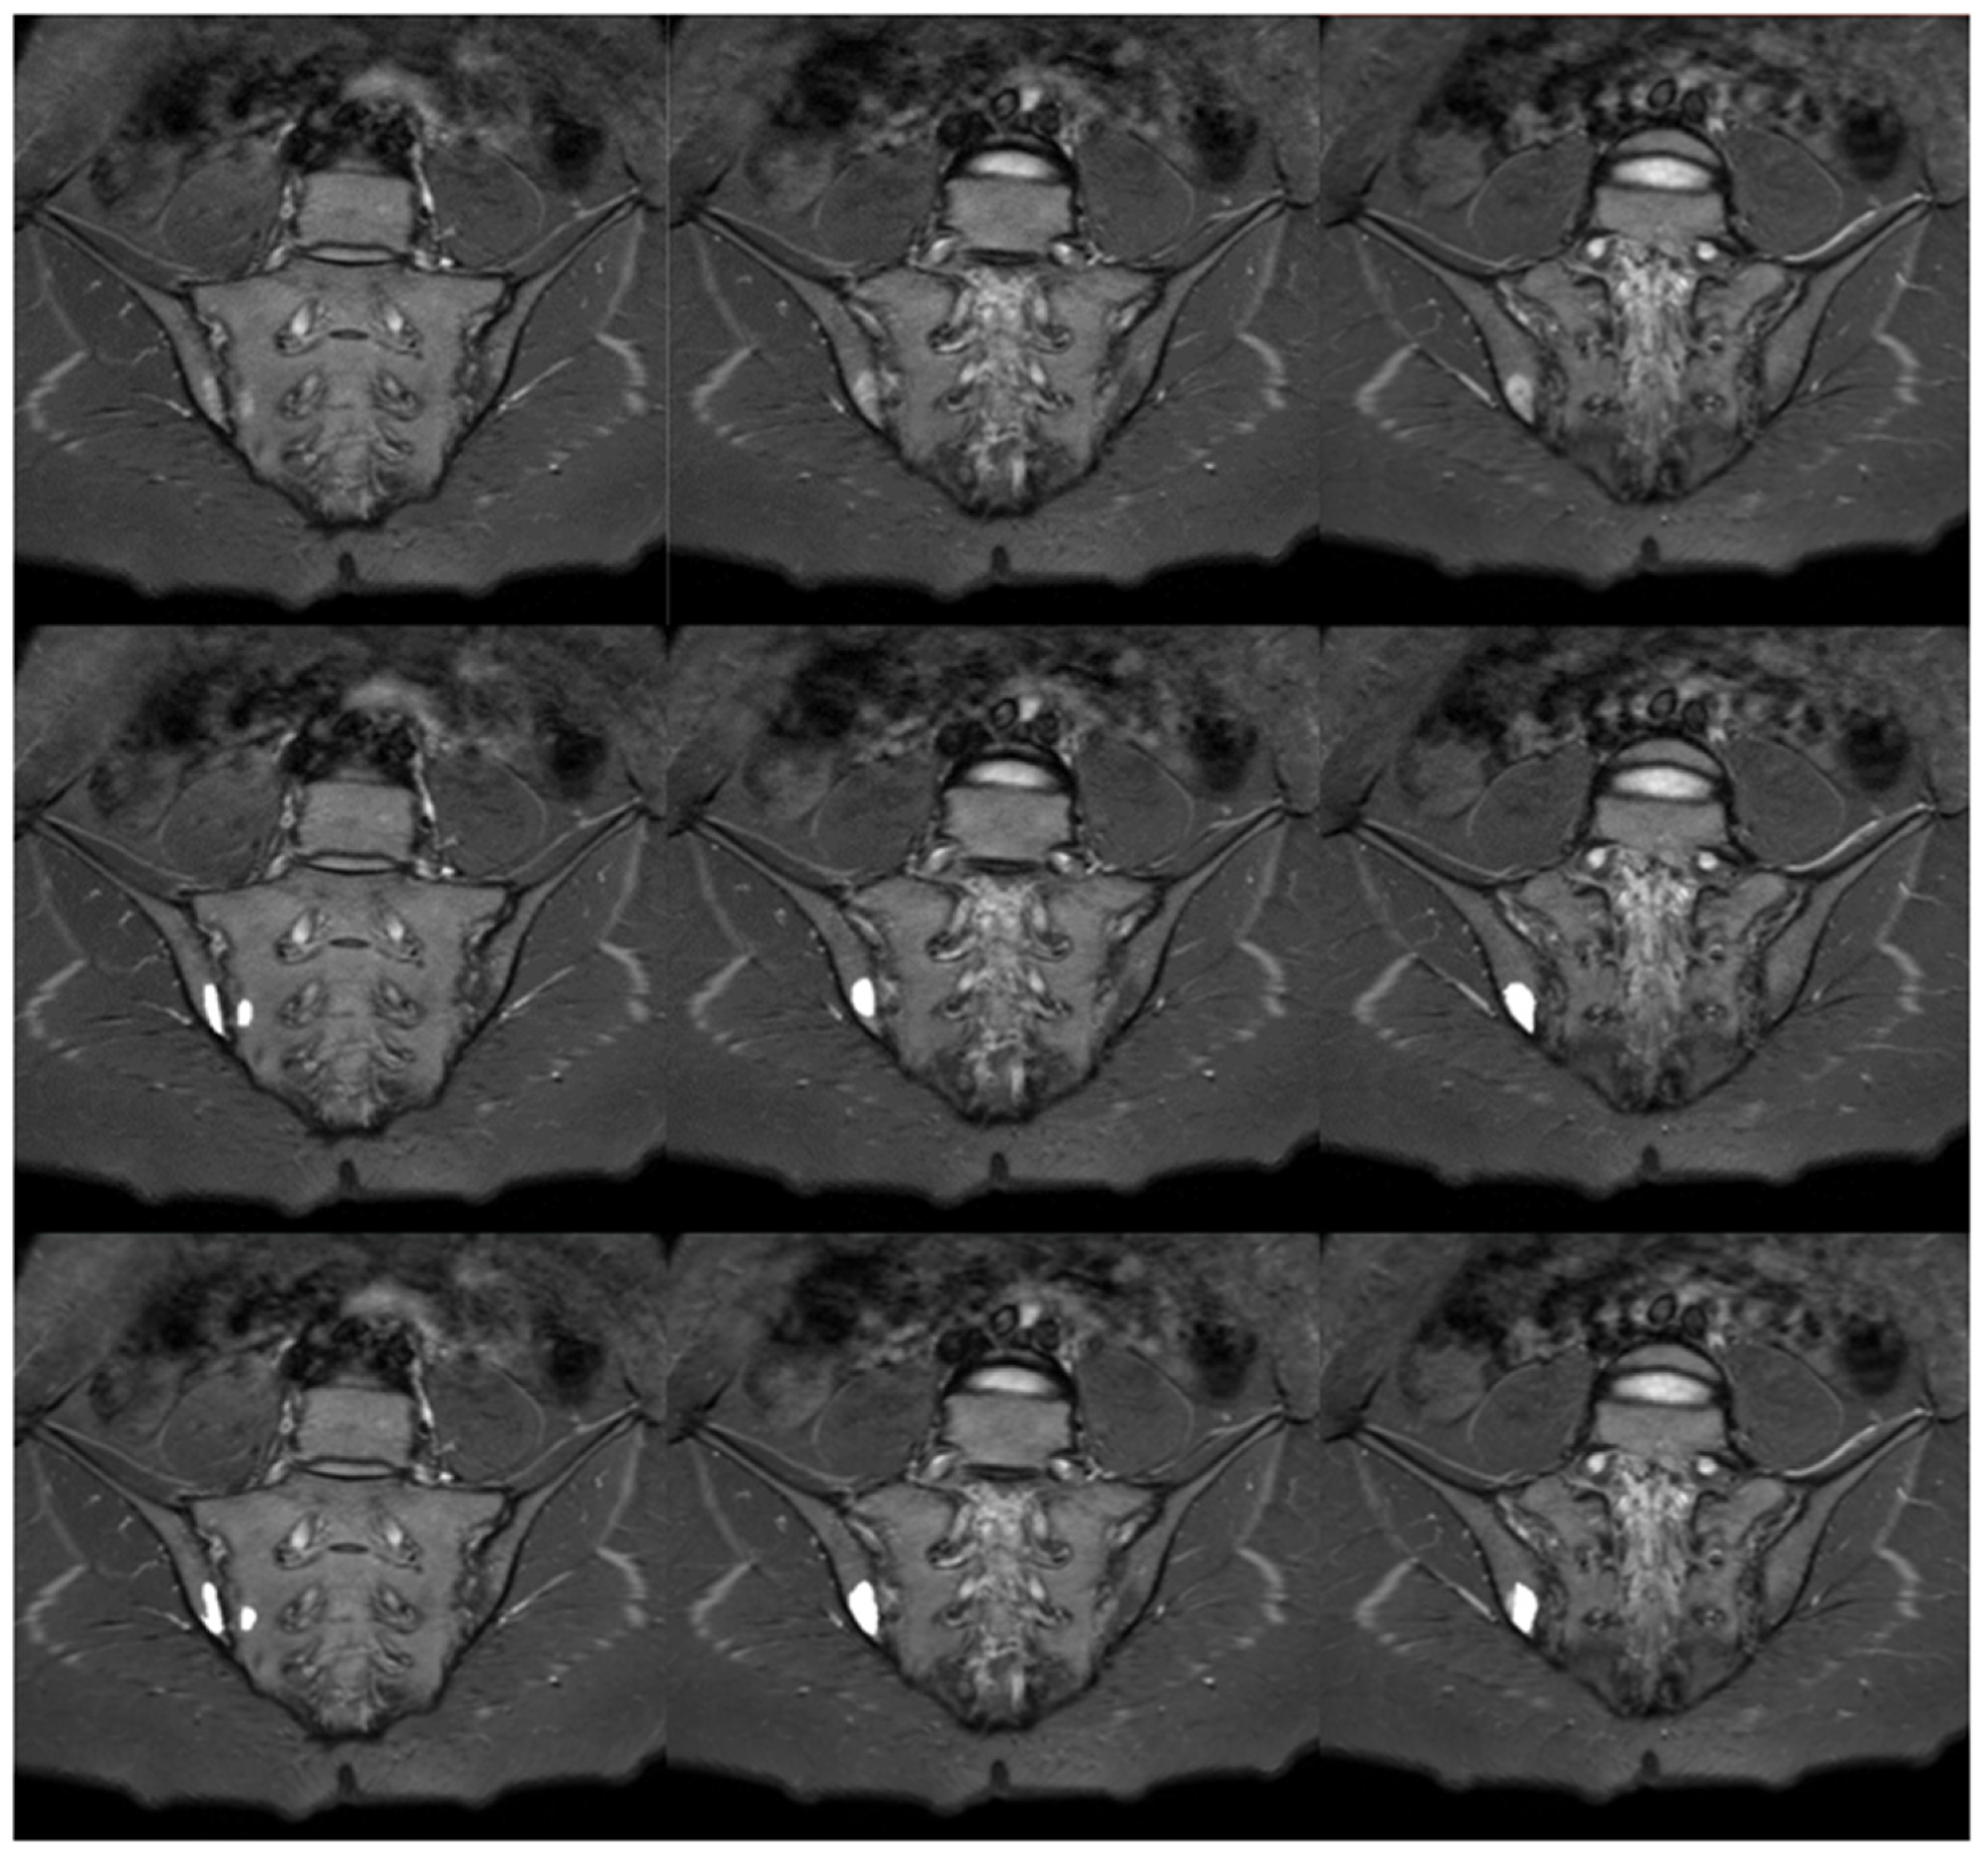

Figure 7.

Sample slices of an average case (visual scale equal to 47, DC = 0.98): T1 sequence in the upper row, manual segmentation in the middle row and automated segmentation in the lower row.

The results of the segmentation of the sacrum and iliac bones are shown in the Table 2. The score awarded by the researcher was calculated for each examination and ranged from 0 to 48 points, with 48 points were awarded in the absence of uncertainty about the complete validity of the automatic segmentation. Fourteen percent (n = 25) of examinations were given 48 points, while the minimum score amounted to 26 points. The median of scores was equal to 47 (IQR, 5). Samples of the manual and automatic segmentations of the sacrum and iliac bones are presented in Figure 7. Kruskal–Wallis H test (H(3) = 0.512, p = 0.9162) was not statistically significant when comparing the results of the visual scale between groups, which suggests no differences in algorithm performance depending on deviation angle value.